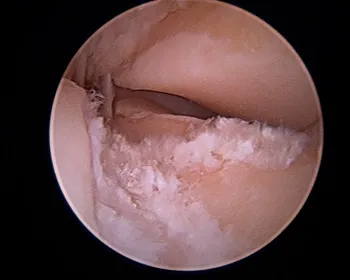

Scar tissue around the Posterior facet

Cleaned out posterior facet